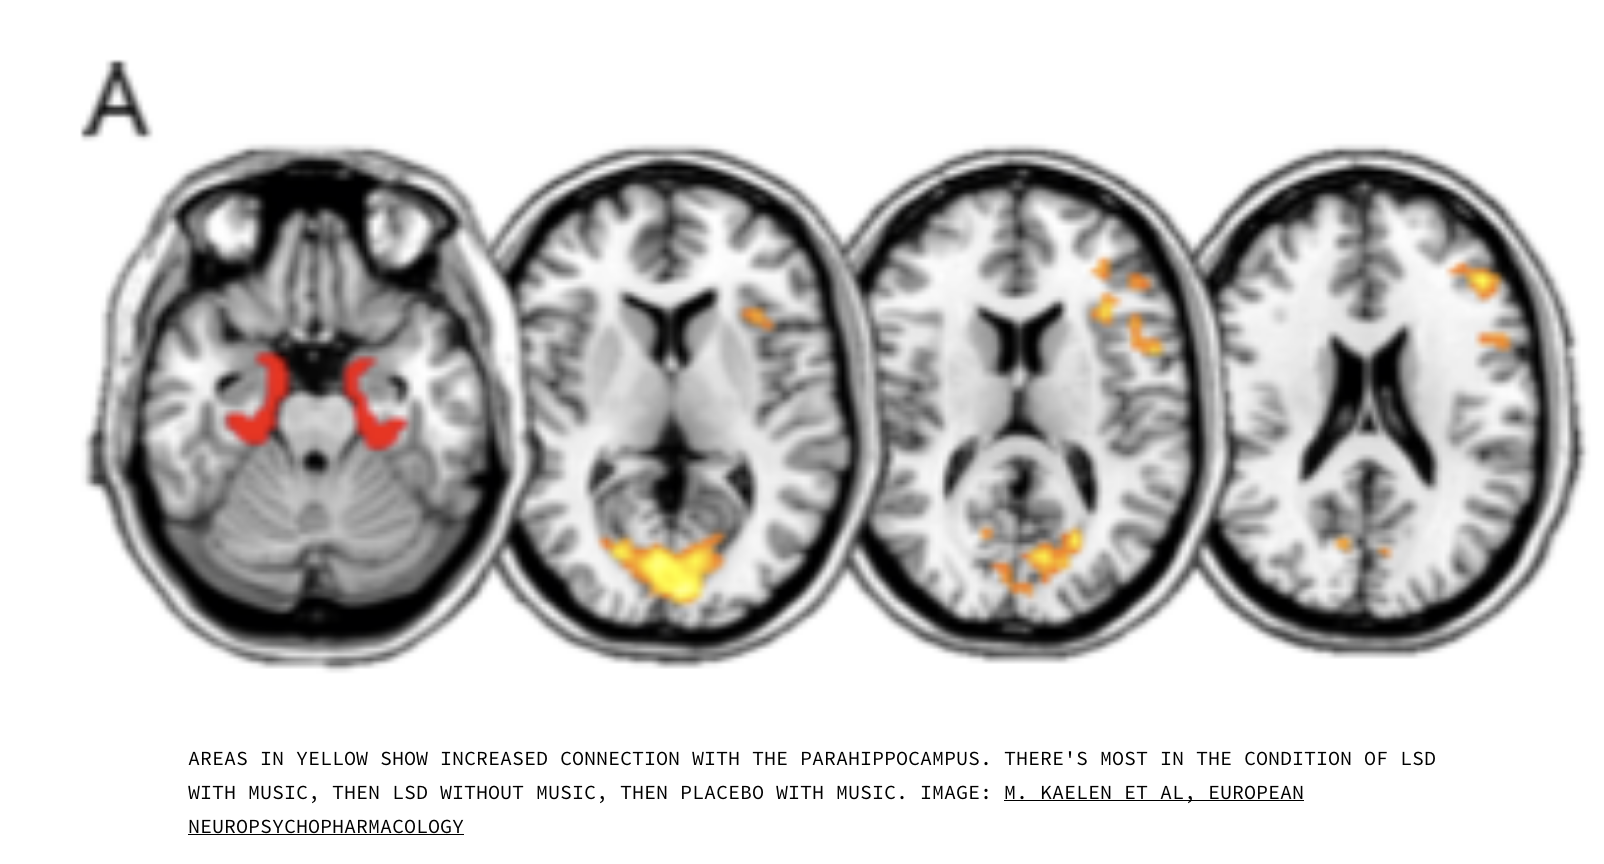

Napjainkban a zene és a pszichedelikus drogok ismét a kutatók érdeklődésének fókuszába kerültek. Az Imperial College kutatói pár éve publikálták kutatásaikat, amelyekben a zene hatásait vizsgálták kérdőívekkel és agyi képalkotó eljárásokkal (fMRI) olyan alanyoknál, akik nagyobb dózisú LSD-t kaptak. A kutatás megerősítette azt, amit Király József már az 50-es években felfedezett: ezek a szerek rendkívüli módon elmélyítik és átalakítják azt a módot, ahogyan az emberi agy a zenét felfogja és értelmezi. Ennek a neurológiai hátteréről ma már többet tudunk, mint Királyék: a pszichedelikus szerek alapvető változást hoznak abban, ahogyan a különféle agyterületek egymással kommunikálnak. A zene hatására például az LSD-fogyasztók agyában az emlékezetért felelős hippokampusz melletti tekervény (gyrus parahippocampalis) és a vizuális kortex közötti intenzív interakciót mutatott ki az agyszkenner. Ez felelős azért, hogy a pszichedelikus élmény csukott szemű látomásokat vált ki a fogyasztókból.